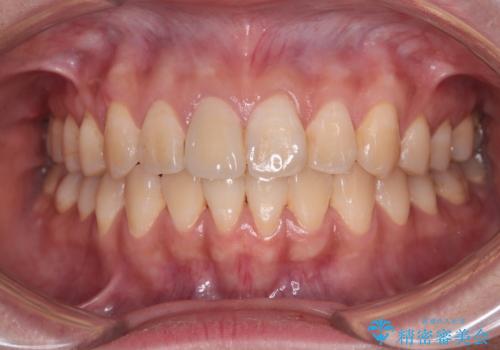

舌の突出癖による開咬と前歯の突出 インビザライン矯正治療

- 上下前歯の非接触と叢生を気にして来院された患者様です。

開咬の改善はインビザラインの最も得意とするところであるため、インビザラインを用いて矯正治療を行うこととしました。

治療開始直後に上顎前歯に激しい痛みが発現し、矯正治療を休んだり、マウスピースの装着時間を短くしたりと工夫をしましたが、残念ながら治療途中で失活していることが分かりました。

矯正治療の途中で前歯の根管治療とオールセラミッククラウンによる補綴治療を行い、その後インビザライン1セットを用いて細かい部分を仕上げました。